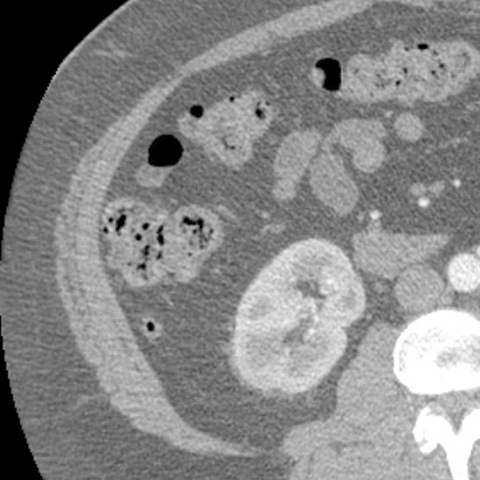

Appendix behind Ascending Colon, CT (axial) [5 of 6]